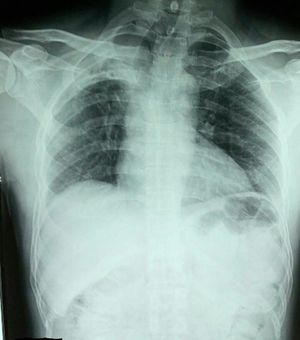

20 yr old male c/o cough and fever since 2 months